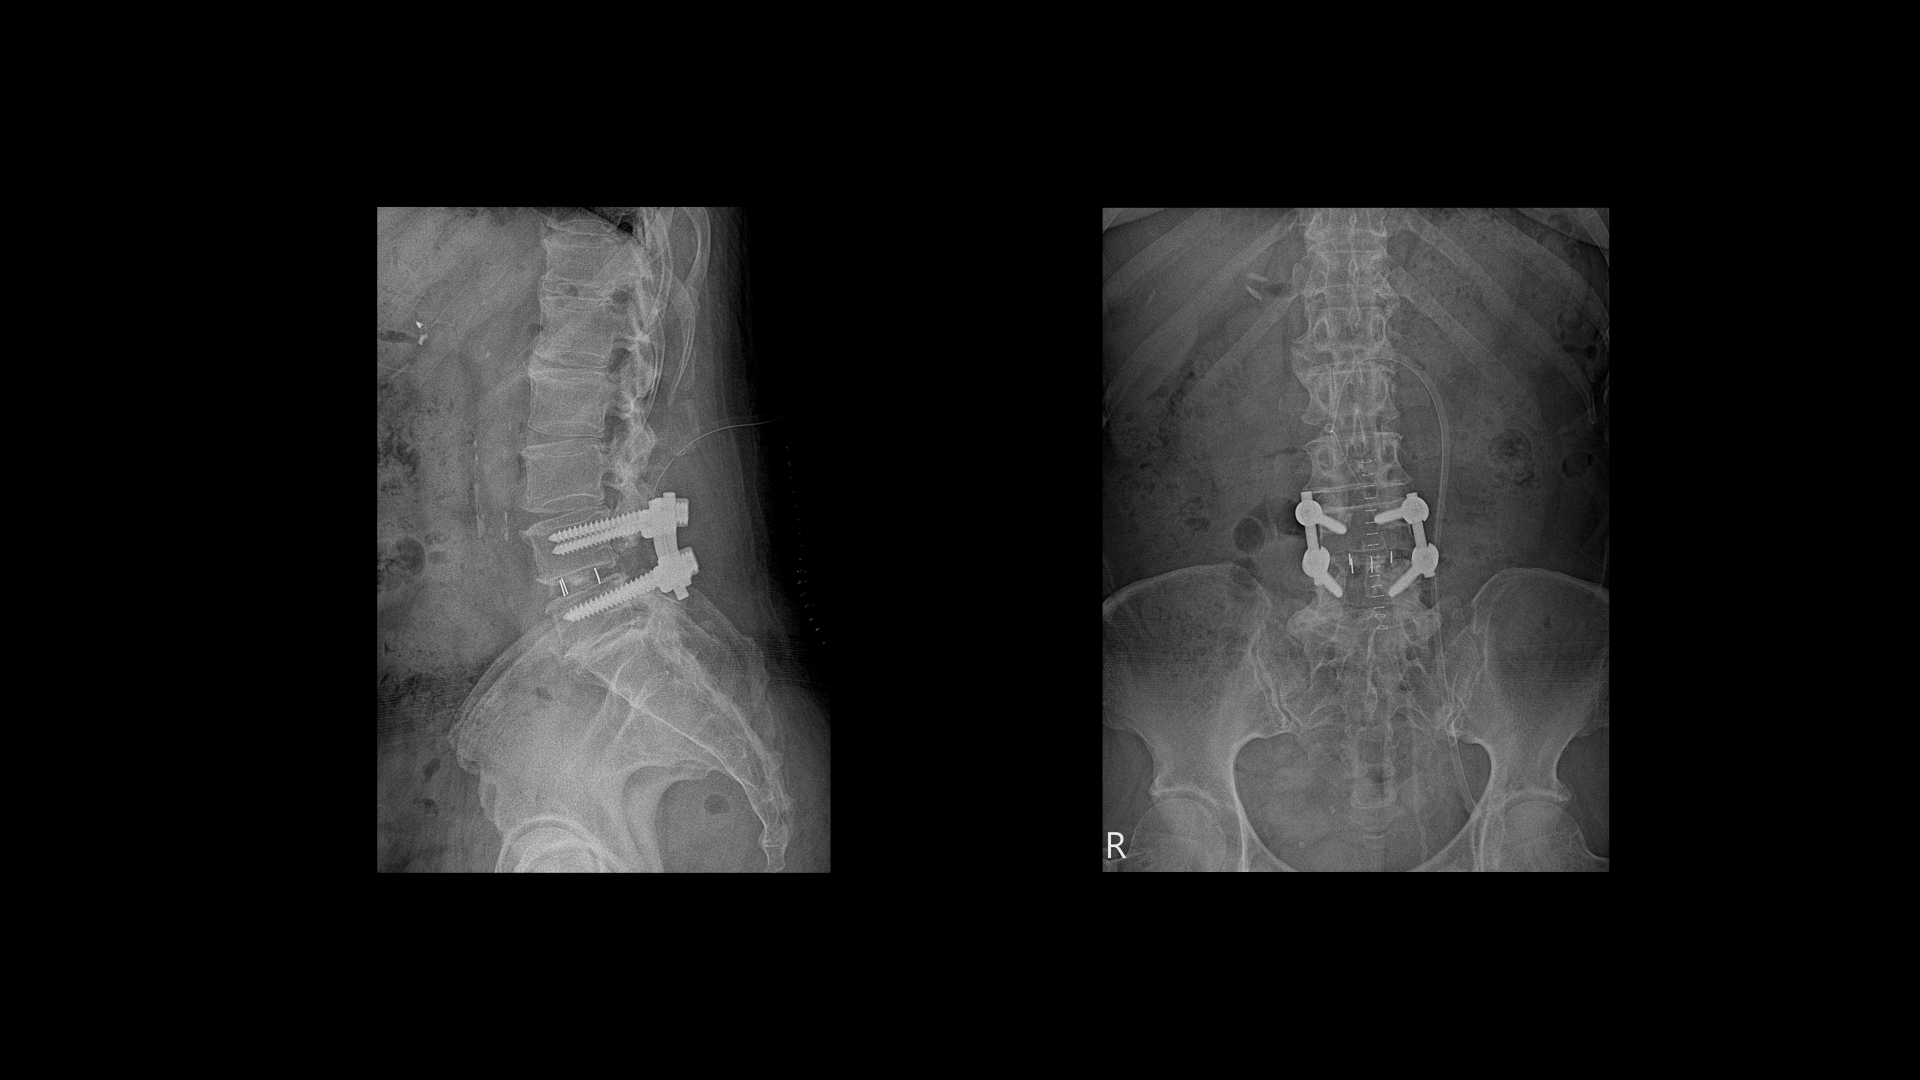

이 환자분은 허리수술을 여러 번 한 상태에서 결국에는 척추유합술까지 하셨습니다. MRI를 보시면 5번 1번 후궁에 수술한 자국이 보입니다.

올해 초에 4번 5번 디스크가 또 오른쪽으로 심하게 파열돼서 결국 후궁과 후관절, 황색인대를 모두 다 제거하고 나사를 박는 척추유합술을 하셨습니다.